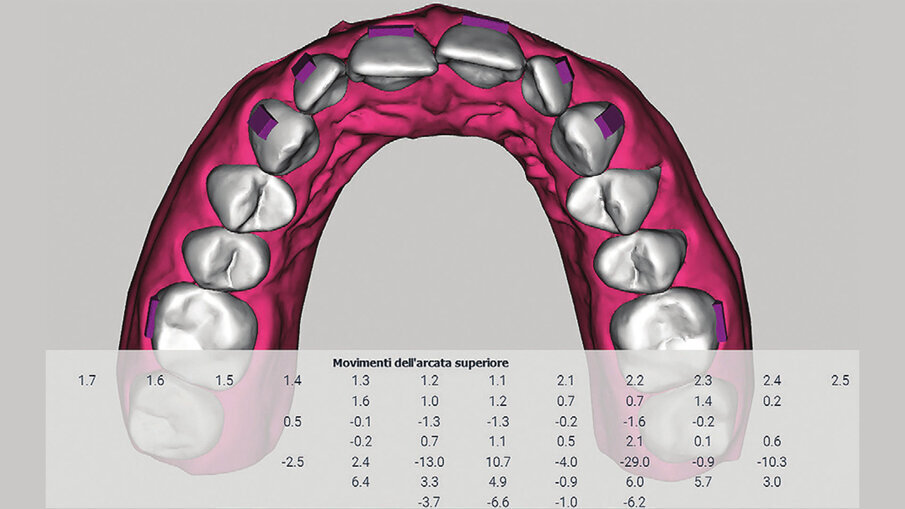

Con View ALLEO (Figg. 5a-5c) avremo la possibilità di analizzare i valori dentali nella tabella dei movimenti; in base ai valori di intrusione e l’ipercorrezione che abbiamo programmato, utilizzeremo una serie di ausiliari che garantiranno il successo e la risoluzione del caso (bite-ramp anteriori, elastici di Classe II, attachments rettangolari orizzontali bisellati gengivalmente o occlusalmente a seconda della direzione della forza). L’utilizzo dei bite-ramp (Fig. 6) anteriori è fondamentale per svincolare le arcate, permettendo l’estrusione posteriore e impedendo l’effetto (in questo caso indesiderato) bite-block degli allineatori. L’intrusione degli incisivi inferiori programmata produrrà sull’allineatore una forza di reazione che tenderà a scalzare posteriormente l’allineatore stesso, tuttavia ciò non avverrà proprio per la presenza di attachments posteriori bisellati occlusamente, che produrranno un’estrusione dei settori posteriori necessaria ad aiutarci nell’apertura del morso (Figg. 7a-7e).

Figg. 5a-5c_View ALLEO ci permette la visualizzazione del set-up, la quantità di stripping necessaria per ottenere un corretto allineamento, la posizione degli attachments, oltre al report biomeccanico preciso di tutti i movimenti dentali proposti all’interno del set-up.

Figg. 5a-5c_View ALLEO ci permette la visualizzazione del set-up, la quantità di stripping necessaria per ottenere un corretto allineamento, la posizione degli attachments, oltre al report biomeccanico preciso di tutti i movimenti dentali proposti all’interno del set-up.

Figg. 5a-5c_View ALLEO ci permette la visualizzazione del set-up, la quantità di stripping necessaria per ottenere un corretto allineamento, la posizione degli attachments, oltre al report biomeccanico preciso di tutti i movimenti dentali proposti all’interno del set-up.

Per la risoluzione del caso sono stati pianificati 30 allineatori superiori e 20 inferiori più una rifinitura successiva, di altri 10 allineatori per arcata, per una durata complessiva di circa 15 mesi di trattamento. Al termine della terapia (Figg. 8a-8h) le arcate si presentano ampie, allineate e ben coordinate; le linee mediane risultano coincidenti, le relazioni occlusali di destra sono state migliorate ottenendo una piena Classe I, mentre a sinistra si raggiunge una buona classe I molare-premolare, lasciando solo il 23 in classe II per non aprire spazi tra l’incisivo laterale. Nonostante l’affollamento fosse moderato, il caso preso in esame mostrava alcune criticità, parliamo della presenza di alcuni elementi dentari in arcata superiore, in particolare del 22 che presentava una rotazione di 29° (vedi Figg. 5a-5c). A tal proposito, la letteratura ci ha ampiamente dimostrato come la derotazione di alcuni elementi dentali in arcata superiore (vedi incisivi laterali) e inferiore (vedi canini e primi premolari), sia uno dei movimenti più difficoltosi da ottenere con la tecnica degli allineatori7.